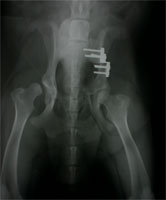

HD vor DBO Operation

Abbildung 2 a: Idealkandidat nach enggefasster Indikationsstellung präoperativ

HD nach DBO Operation

Abbildung 2 b: Der selbe Patient nach DBO. Die Spuren einer erfolglosen Goldakupunktur-Therapie sind zu erkennen.